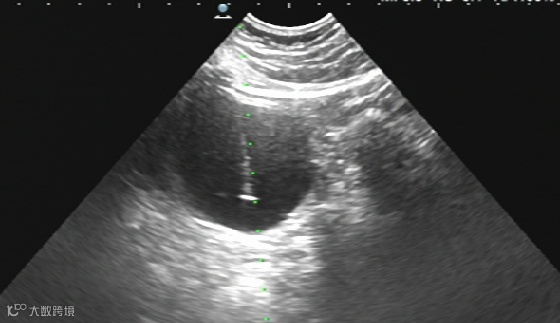

左肾囊肿硬化治疗:

治疗前

治疗后